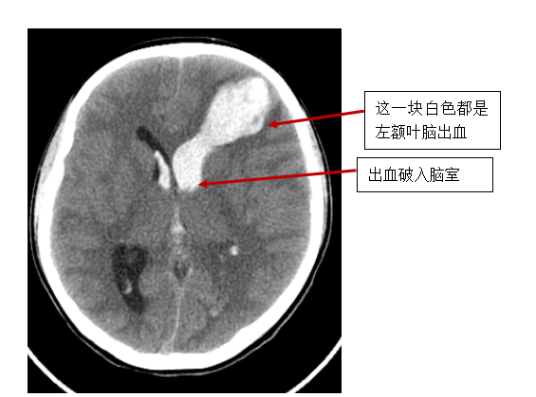

小孙的头颅CT明确提示:左额叶脑出血并破入脑室系统。小孙比较年轻,也没有高血压基础病,属于自发性脑内出血。

结合其他诊断,医生考虑小孙存在脑动静脉畸形的可能性很大,需要做头颅CTA(CT血管成像)。

很快,小孙的头颅CTA(CT血管成像)检查结果明确提示:左额叶侧脑室旁“动静脉畸形”。